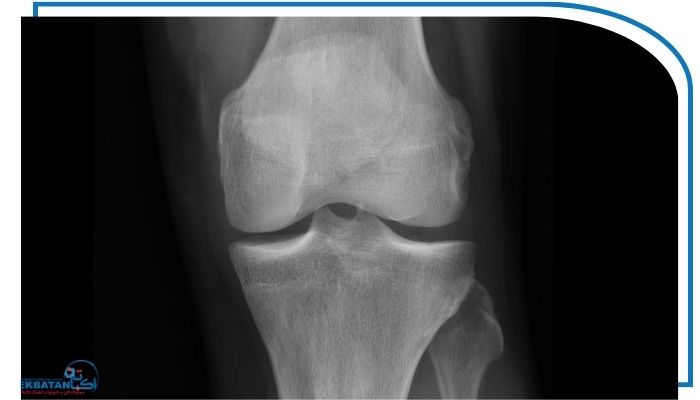

تفاوت با سایر روش های تصویربرداری

در رادیوگرافی ساده معمولاً فقط یک مفصل بررسی می‌شود. اما در رادیوگرافی تری جوینت سه مفصل حیاتی اندام تحتانی به صورت یکپارچه در یک تصویر ثبت می‌شوند. این تفاوت باعث می‌شود پزشک بتواند تأثیر مشکلات یک مفصل بر سایر مفاصل را ارزیابی کند.

از طرفی رادیوگرافی tree joint نسبت به روش‌هایی مانند MRI و CT اسکن مزایای زیر را دارد:

سرعت بالا در تصویربرداری و تحویل نتایج

هزینه کمتر برای بیماران

قابلیت استفاده به عنوان اولین قدم در تشخیص مشکلات اسکلتی

البته باید توجه داشت که برای بررسی بافت‌های نرم مثل رباط‌ها یا عضلات، همچنان MRI انتخاب مناسب‌تری است.